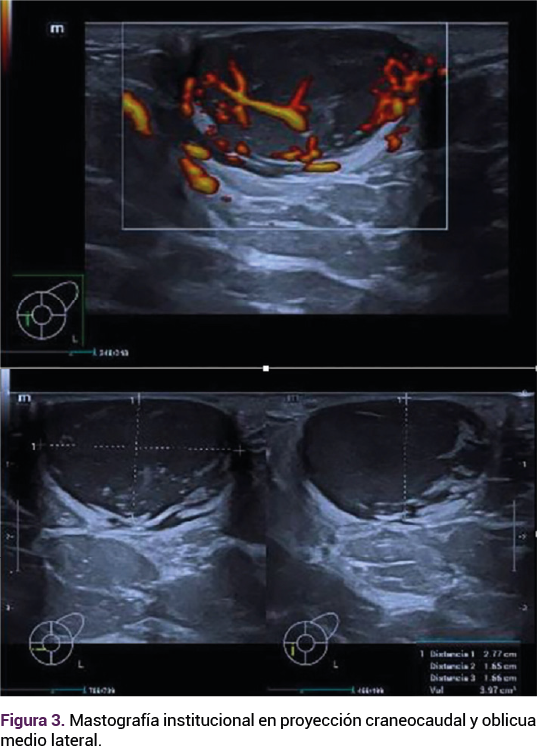

La ecografía (Figura 2) y mastografía (Figura 3) institucional reportaron: mama izquierda BIRADS 4A, nódulos sólido-quísticos (que requieren toma de biopsia), calcificaciones típicamente benignas, ganglios inflamatorios y la mama derecha con BIRADS 2.

<strong>Figura 3</strong>

Figura 3.